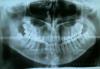

manul Опубликовано 18 ноября, 2010 Поделиться Опубликовано 18 ноября, 2010 Здравствуйте. Примерно год назад начала немного щелкать челюсть с левой стороны, одновременно с ростом восьмерок. Примерно полгода назад восьмерки с левой стороны снизу и сверху прорезались частично, но с этого же времени не могу полностью открыть рот - началась сильная боль слева и периодически не только при открывании рта, время от времени иррадирует в ухо. Плюс ощущение, что два передних резца подвижны. Сделала ортопанорамный снимок. Хирург в районной стоматологической поликлинике наорал на меня, что мол "Начитаются в интернете про зубы мудрости! Всё это ерунда! Всё у вас отлично! Надо орехи грызть, семечки и яблоки! Отличный прикус!"Поверила, что надо ждать, пока зубы вылезут. Но потом услышала по радио, что если щелкает челюсть, надо бежать к ревматологу. Прибежала. Ревматолог посмотрел ортопанорамный снимок, направил на рентген челюстного сустава, тк на орто его не видно. В рентгене ответили, что челюстной сустав у них не снимают - нет такого аппарата, надо делать орто. Говорю, что орто сделано уже, но сустава там не видно. Бабка из рентгена говорит, что у них обычный рентгеновский аппарат, на котором позвоночник и т.п. снять можно, а сустав челюстной - нет, нужен специальный аппарат. В стоматологических клиниках говорят, что делают только орто, никаких суставов. Какой-то бред. Теперь я что-то совсем не понимаю, что мне делать и к кому идти? И что можете сказать по снимку? Спасибо заранее. Ссылка на комментарий

manul Опубликовано 20 ноября, 2010 Автор Поделиться Опубликовано 20 ноября, 2010 (изменено) Большое спасибо.Добавляю снимок ВНЧС. Рентгенолог написал: головка мыщелкового отростка справа несколько ремоделирована, контуры ее неровные, нечеткие; слева без особенностей. На r-граммах, выполненных с открытым ртом головка мыщелкового отростка справа проецируется у переднего ската суставного бугорка, слева ближе к заднему скату. Суставная щель справа незначительно сужена. Косвенные признаки артрита-артроза справа. Изменено 20 ноября, 2010 пользователем manul Ссылка на комментарий